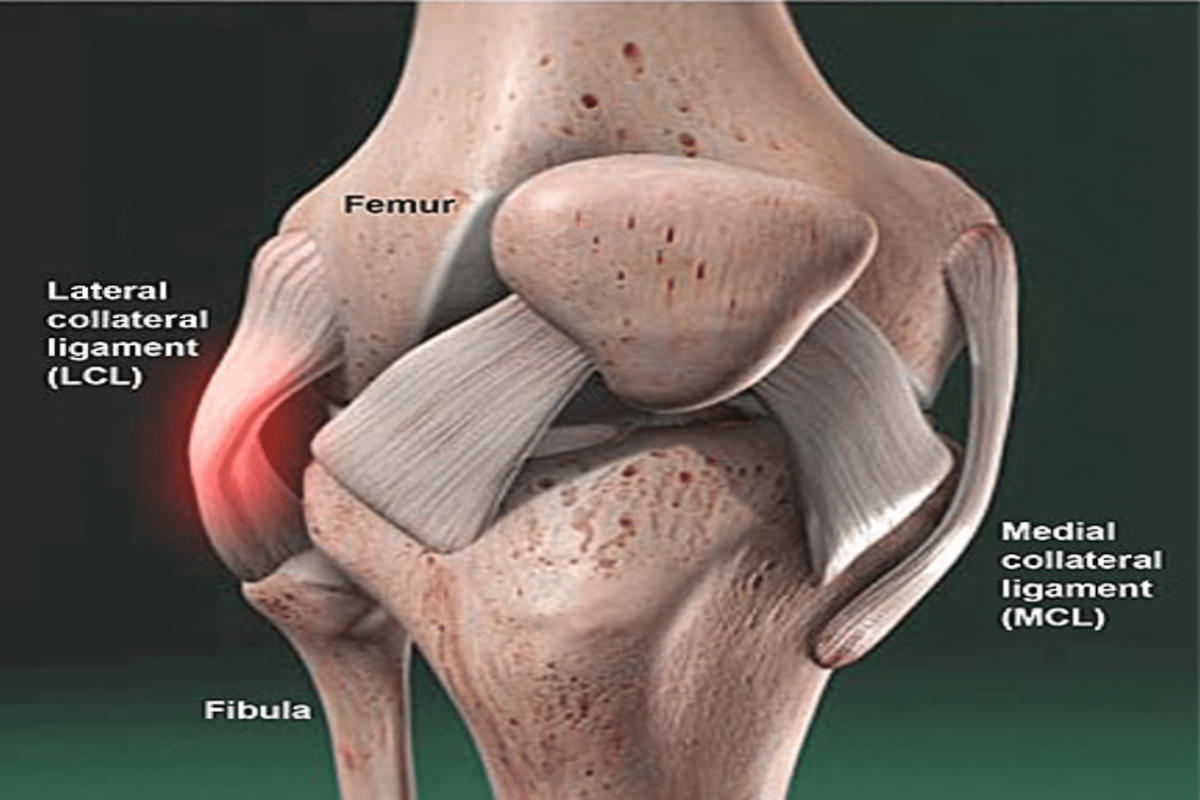

Ο έσω πλάγιος σύνδεσμος (MCL) βρίσκεται στην εσωτερική πλευρά του γόνατος και εμποδίζει την απόκλιση της άρθρωσης προς τα μέσα. Ο έξω πλάγιος σύνδεσμος (LCL) εντοπίζεται στην εξωτερική πλευρά και προστατεύει από δυνάμεις που ωθούν το γόνατο προς τα έξω.

Ο τραυματισμός του έσω πλαγίου συνδέσμου είναι συχνότερος, ενώ η ρήξη του έξω πλαγίου συνδέσμου συνήθως σχετίζεται με σοβαρότερες κακώσεις και συχνά συνοδεύεται από βλάβες άλλων συνδέσμων, όπως ο πρόσθιος χιαστός σύνδεσμος.